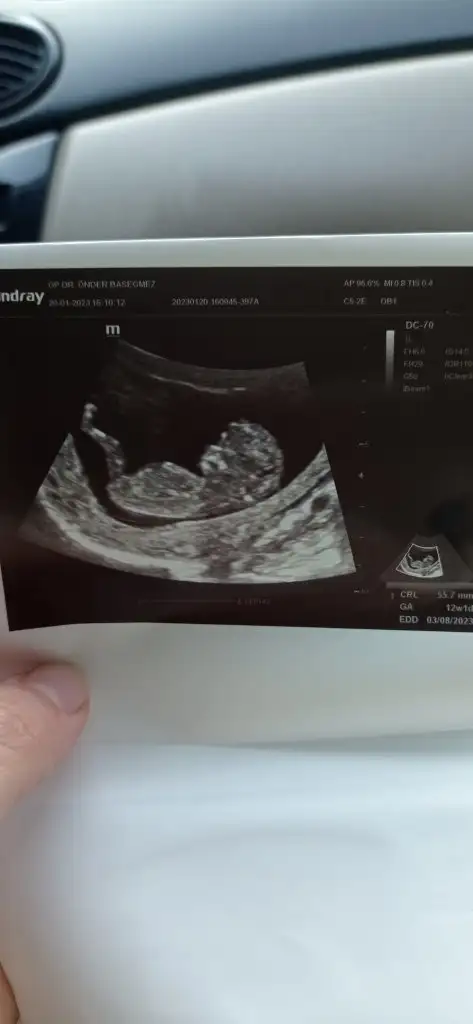

Bende tahmin istiyorum 8haftalik fotolarimiz bunlar

• IMG20230130153027.webp

IMG20230130153027.webp

23,6 KB · Görüntüleme: 78